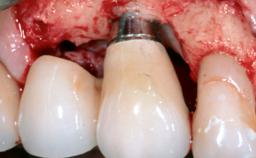

Treatment of Peri-Implantitis at a Zirconia Implant

Frank Schwarz, Ausra Ramanauskaite

Due to their promising clinical performance, zirconia implants have recently become popular alternatives to titanium implants, particularly for areas with high esthetic demands (Holländer and coworkers 2016; Roehling and coworkers 2016; Lorenz and coworkers 2019). However, regardless of the reported high survival and success rates, zirconia implants were affected by peri-implant diseases over the short observation period, suggesting the importance of treating peri-implant diseases at zirconia implants (Becker and coworkers 2017). In their case, Frank Schwarz and Ausra Ramanauskaite present 3-year results following mechanical debridement alongside Er:YAG laser monotherapy.